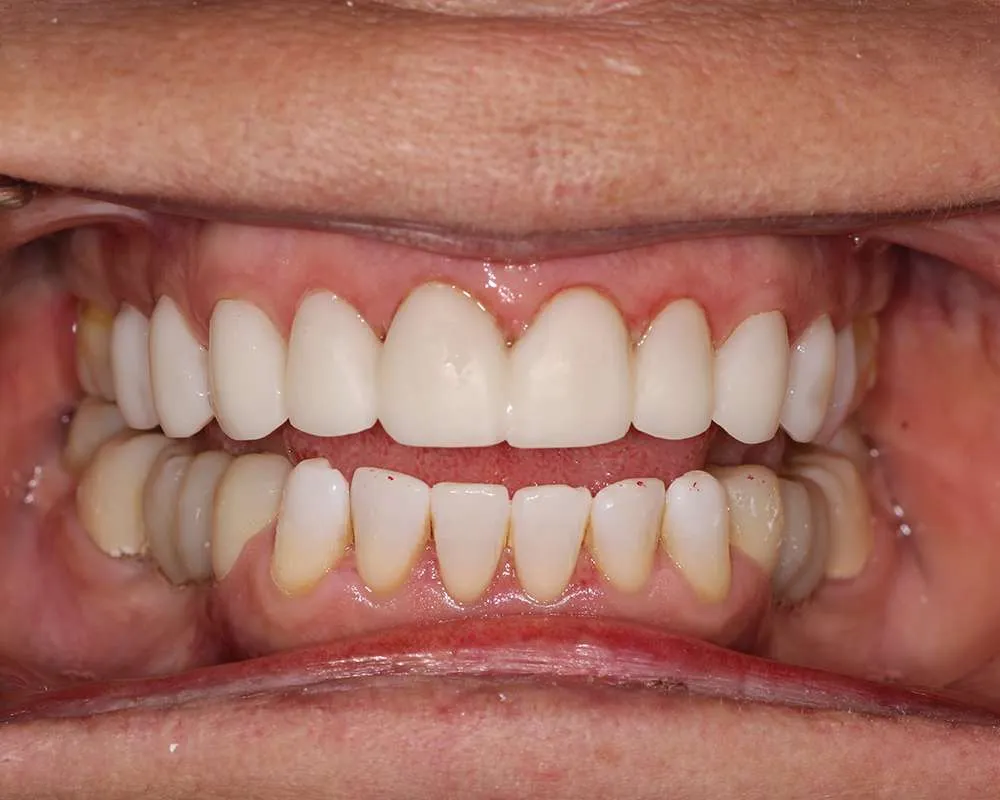

Real Stories, Real Results: Case Studies Showcasing How Our Personalized Approach Transforms Smiles and Lives

Complex Cases

Witness the Remarkable Changes We Can Achieve